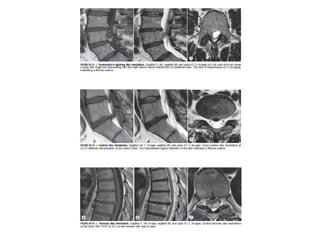

The spine is made up of vertebrae separated by intervertebral discs that allow movement and provide shock absorption. Diagnostic imaging plays an important role in evaluating the spine for conditions like fractures, disc herniations, spinal stenosis, and tumors. Imaging modalities like X-rays, CT scans, MRI, and bone scans can detect abnormalities and aid physicians in diagnosing and treating various spinal disorders.